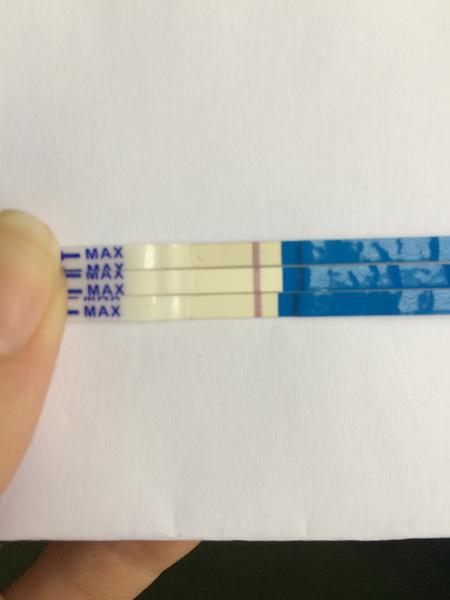

První byl ClearBlue a téměř hned tam naskočilo plus.

Udělal jsem radši ještě jeden - jmenuje se ForYou... Tam se objevil slabý duch, ale až tak za 3minuty! Šla jsem ven se psi a když jsem se vrátila, tak duch byl silnější...no ale to bylo skoro po půl hodině!

Tak nevim ... ☹ Dávám fotku, skuste posoudit...

- Slabá druhá čárka na domácím těhotenském testu může znamenat velmi časné těhotenství, biochemické těhotenství nebo vliv ředění moči a různou citlivost testů; spolehlivější potvrzení poskytne opakované testování z první ranní moči a krevní odběr hCG.

- V diskuzi byly zmíněny konkrétní citlivosti testů (ClearBlue 25 mIU/ml, ForYou 20 mIU/ml, RapidClear 10 mIU/ml) a zároveň varování, že intenzita čárky závisí na značce, množství barviva v testu a koncentraci moči, takže srovnávání čárek mezi různými testy je nespolehlivé.

A: Intenzita čárky závisí na koncentraci moči (nejkoncentrovanější je ranní moč), na množství barviva v konkrétním testu a na množství hCG v krvi; v diskuzi také zaznělo, že čárka může být slabá v časném těhotenství nebo při biochemickém těhotenství.

A: Několik příspěvků varovalo, že čtení výsledků mimo doporučený čas může ukázat „ducha“ vlivem zaschnutí nebo chemických reakcí; spolehlivý výsledek je ten uvedený v návodu testu v doporučeném časovém okně.